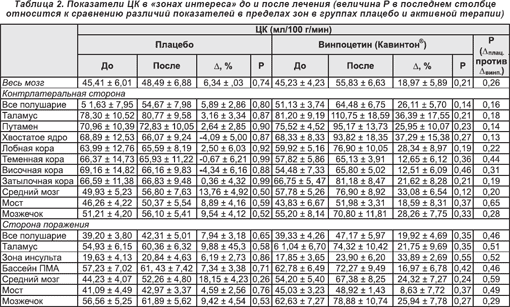

Показатели общего ЦК во всей группе пациентов до лечения составляли 45,33 ± 3,63 мл/100 г/мин. Существенных различий исходных величин общего ЦК между группами плацебо и активной терапии винпоцетином (Кавинтоном®) не имелось (45,41 ± 6,01 мл/100 г/мин и 45,23 ± 4,23 мл/100 г/мин соответственно). Значения параметра после 14 суток терапии составили 48,49 ± 6,88 мл/100 г/мин среди реципиентов плацебо и 55,83 ± 6,63 мл/100 г/мин после применения винпоцетина (Кавинтона®). Различия были недостоверны (p = 0,74 и 0,21 соответственно).

Наибольшее увеличение кровотока после терапии в группе плацебо обнаруживалось в среднем мозге (13,76 ± 4,92%), мосте (8,89 ± 4,16%) и мозжечке (9,54 ± 4,12%), в то время как в группе активной терапии таковое определялось в тех же структурах (средний мозг — 33,08 ± 6,54%, мост — 18,59 ± 8,31%, мозжечок — 28,26 ± 7,75), а также неповрежденном таламусе (36,39 ± 17,55), хвостатом ядре (37,29 ± 15,38%) и зоне инсульта (33,89 ± 2,69%) (таблица 2, рисунки 2 и 3). Тест ANOVA с трехсторонним взаимодействием показал несомненную тенденцию к увеличению показателей ЦК после лечения при особой заинтересованности таламуса (F(5,55) = 1,81; p < 0,12). Тем не менее, обусловленные терапией изменения в контрлатеральной гемисфере после применения винпоцетина (Кавинтона®) характеризовались отчетливой тенденцией к более выраженному повышению (величины p в пределах от 0,12 до 0,46), нежели в группе плацебо (от 0,50 до 0,99 соответственно) (таблица 2). Сравнение различий показателей кровотока (группа плацебо/до и после лечения и соответствующие величины в группе получавших винпоцетин (Кавинтон®)) также показало четкую тенденцию, а именно что интенсификация кровотока в группе активной терапии характеризуется тенденцией к отчетливому превышению таковой в группе плацебо (для базальных ганглиев, таламуса, среднего мозга, затылочной и лобной коры, а также всего незаинтересованного полушария p < 0,25).

Несмотря на отсутствие достоверности изменений по уровню p < 0,05, имелись заметные различия степени увеличения ЦК в двух группах, что проявлялось как большим диапазоном изменений, так и явно меньшими значениями Р согласно ANOVA и t-критерию в группе активной терапии (таблица 2).

Увеличение показателей ЦК в группе получавших винпоцетин (Кавинтон®) было в различных участках головного мозга неоднородным. В контрлатеральном полушарии показатель был явно выше в большинстве мозговых структур. Увеличение было наибольшим в тканях таламуса, хвостатого ядра и среднего мозга. При этом винпоцетин (Кавинтон®) повышал наиболее заметно ЦК в области хвостатого ядра (37,29%), таламуса (36,39%) и среднего мозга (3,08%), далее в ряду располагались мозжечок, лобная область коры, путамен и затылочная кора больших полушарий. Эти структуры головного мозга соответствуют зонам, где обнаруживается наибольший захват [11C]-винпоцетина (Кавинтона®) как у лабораторных обезьян [21], так и у человека [22, 23, 25]. Этот факт может указывать на выраженную связь фармакологических и физиологических эффектов препарата в некоторых структурах мозга. В действительности, усиление перфузии в неповрежденной ткани после ишемического инсульта было описано ранее на основании определения параметров регионального церебрального кровотока методом ПЭТ (см. напр. [51]).

В заинтересованном полушарии имело место увеличение ЦК во всех структурах как после контрольной инфузии, так и после введения винпоцетина (Кавинтона®). Аналогично данным в отношении незаинтересованного полушария, в большинстве структур увеличение ЦК после инфузии винпоцетина (Кавинтона®) было более заметным, нежели в результате введения изотонического солевого раствора. Это явление было особо выраженным в зоне инсульта (33,89%), таламусе (21,75%), среднем мозге (24,32%) и мозжечке (25,94%), что указывает на перераспределение кровоснабжения между структурами головного мозга под влиянием винпоцетина (Кавинтона®).